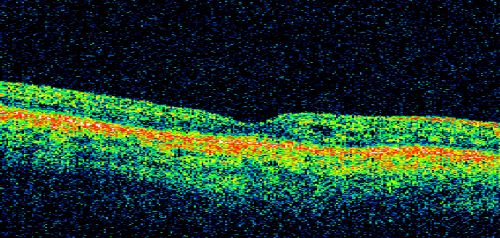

Basal Laminar Drusen - Cuticular Drusen - Equatorial Drusen - 70 Year Old Woman - OCT Line Scan Right Eye

70 year old woman has had macular drusen since her thirties and she said her sister has a similar problem.  Recently the vision in the left eye has substantially declined. OD 20/16, OS 10/200.